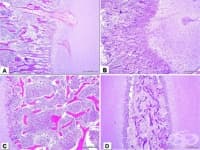

Метаплазия